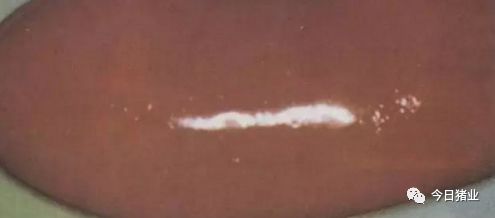

11.肝坏死灶

△【猪伪狂犬病】肝坏死灶